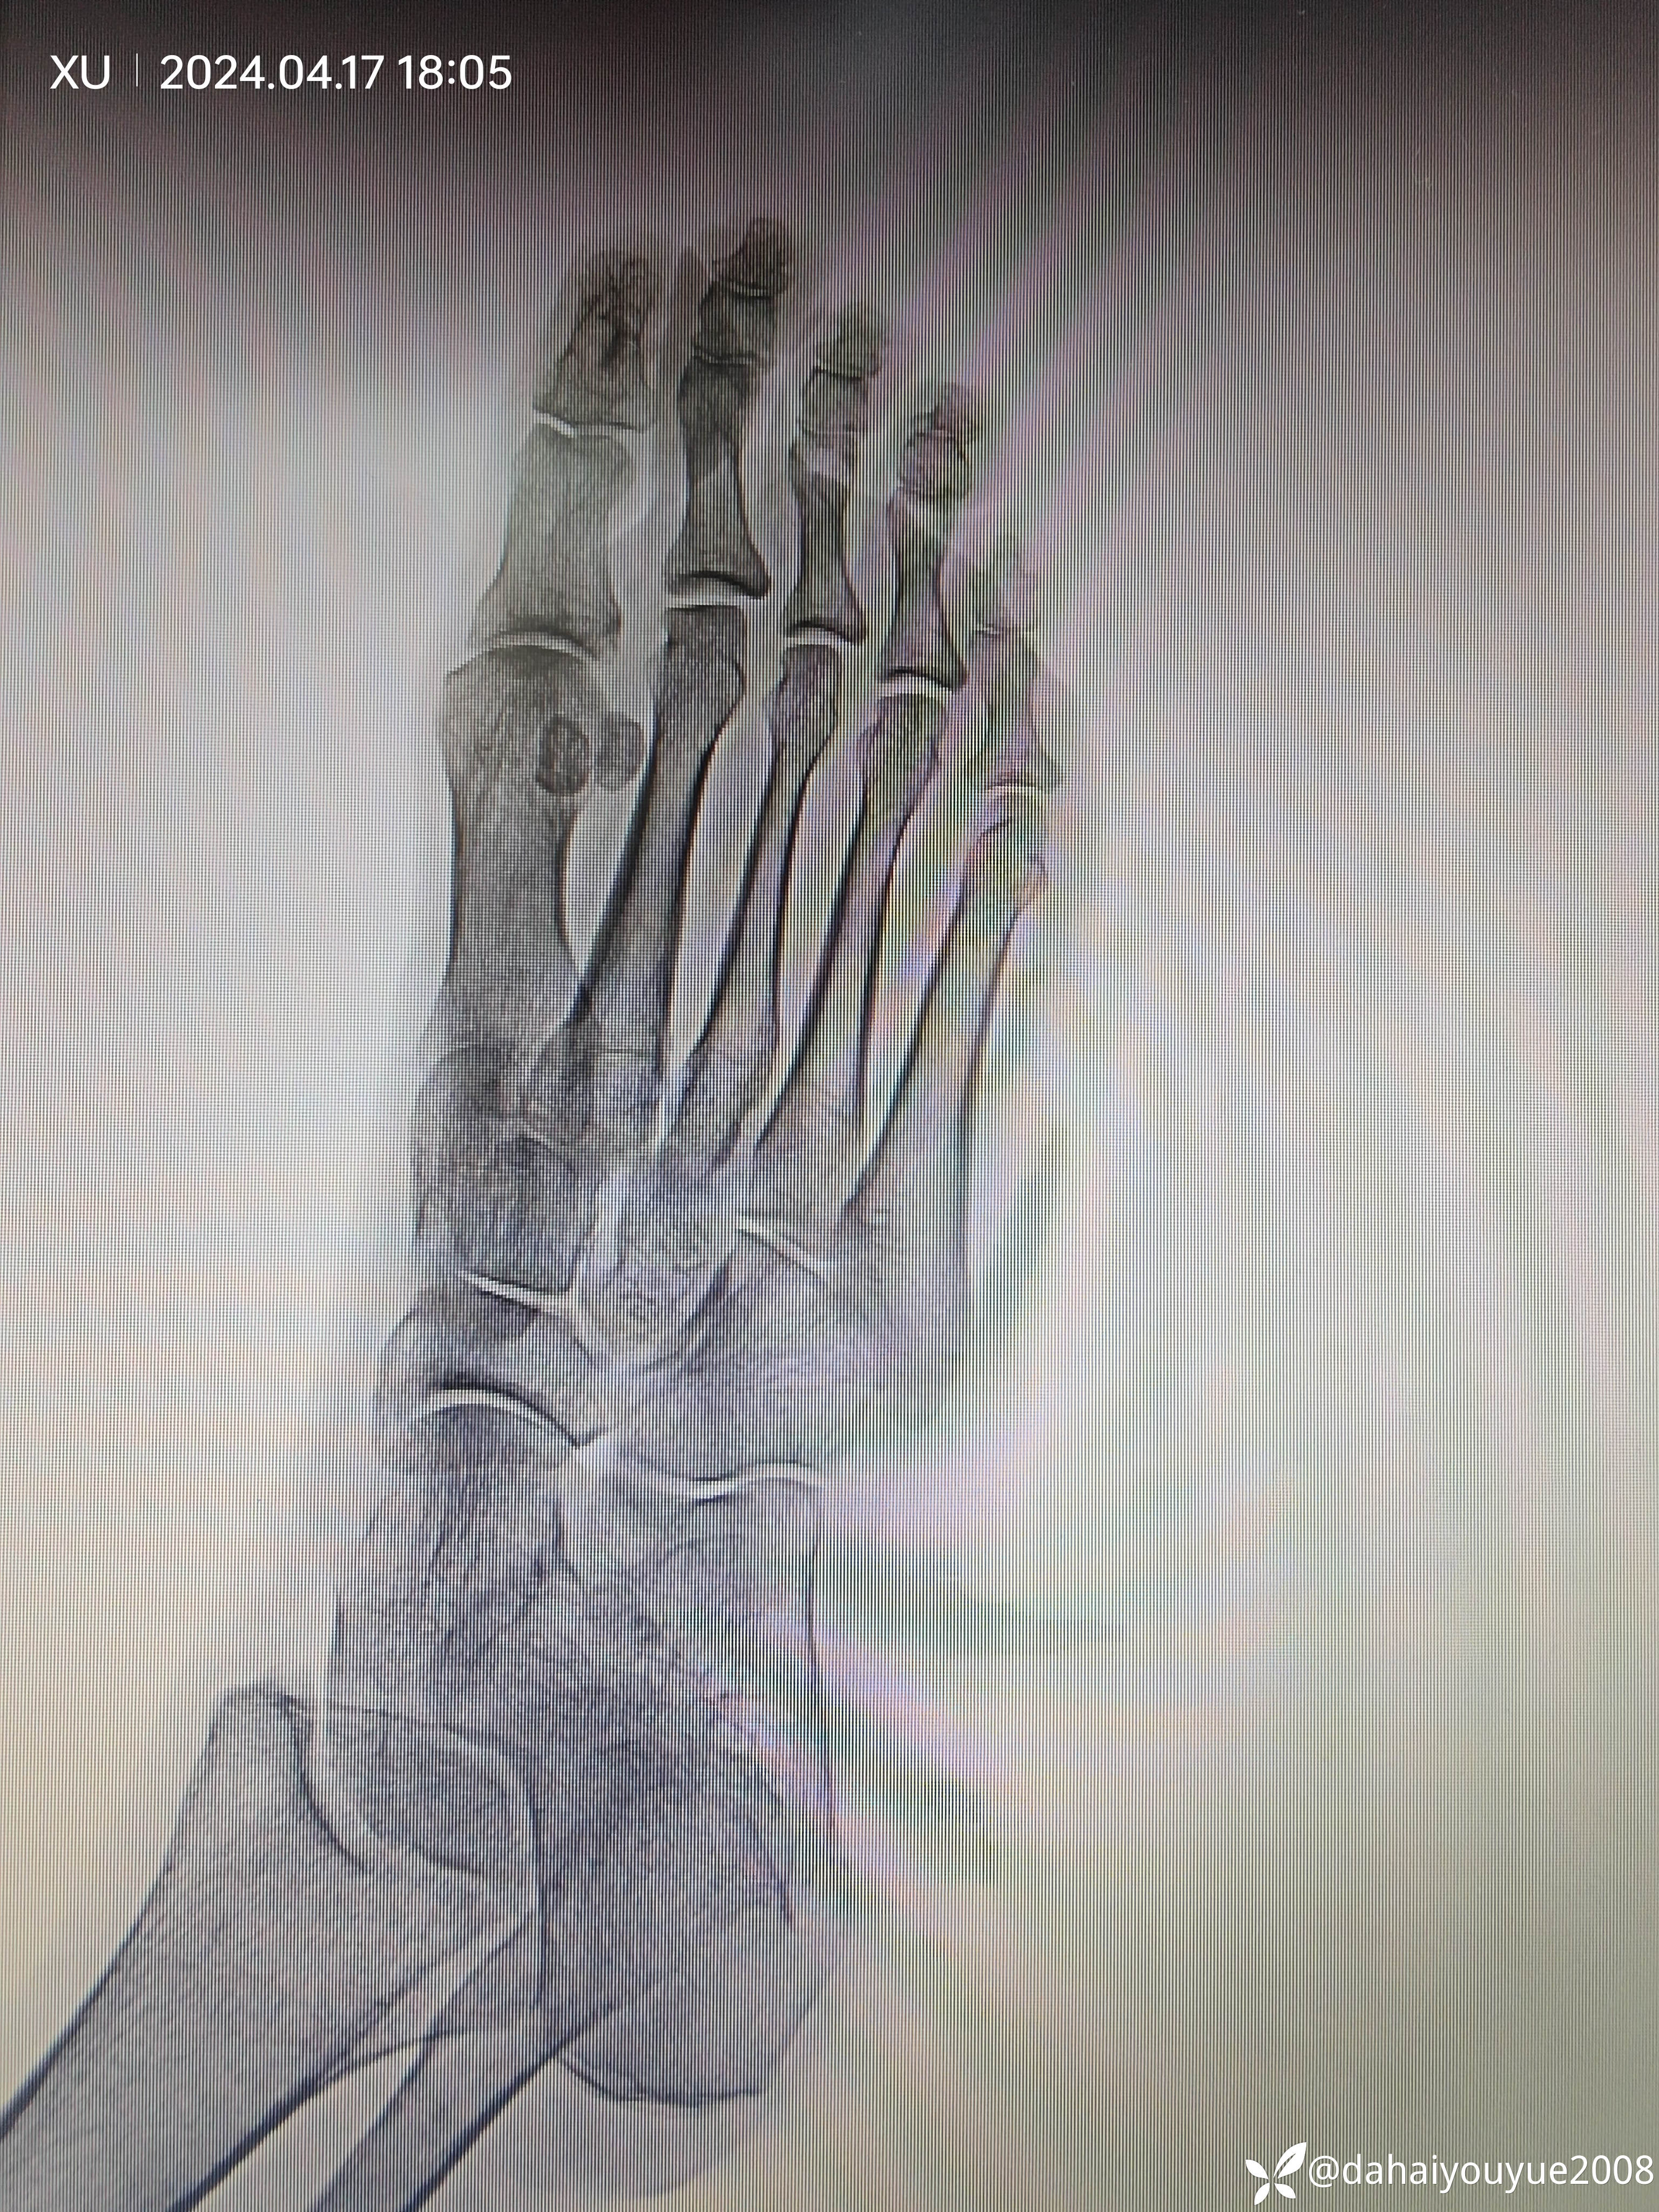

病例1:入院查体:右拇趾未节主动伸直不能,伸趾无力,趾体屈曲。考虑拇长伸肌腱断裂。肌骨超声示:拇长伸肌腱断裂。拍片:未见骨折征象。